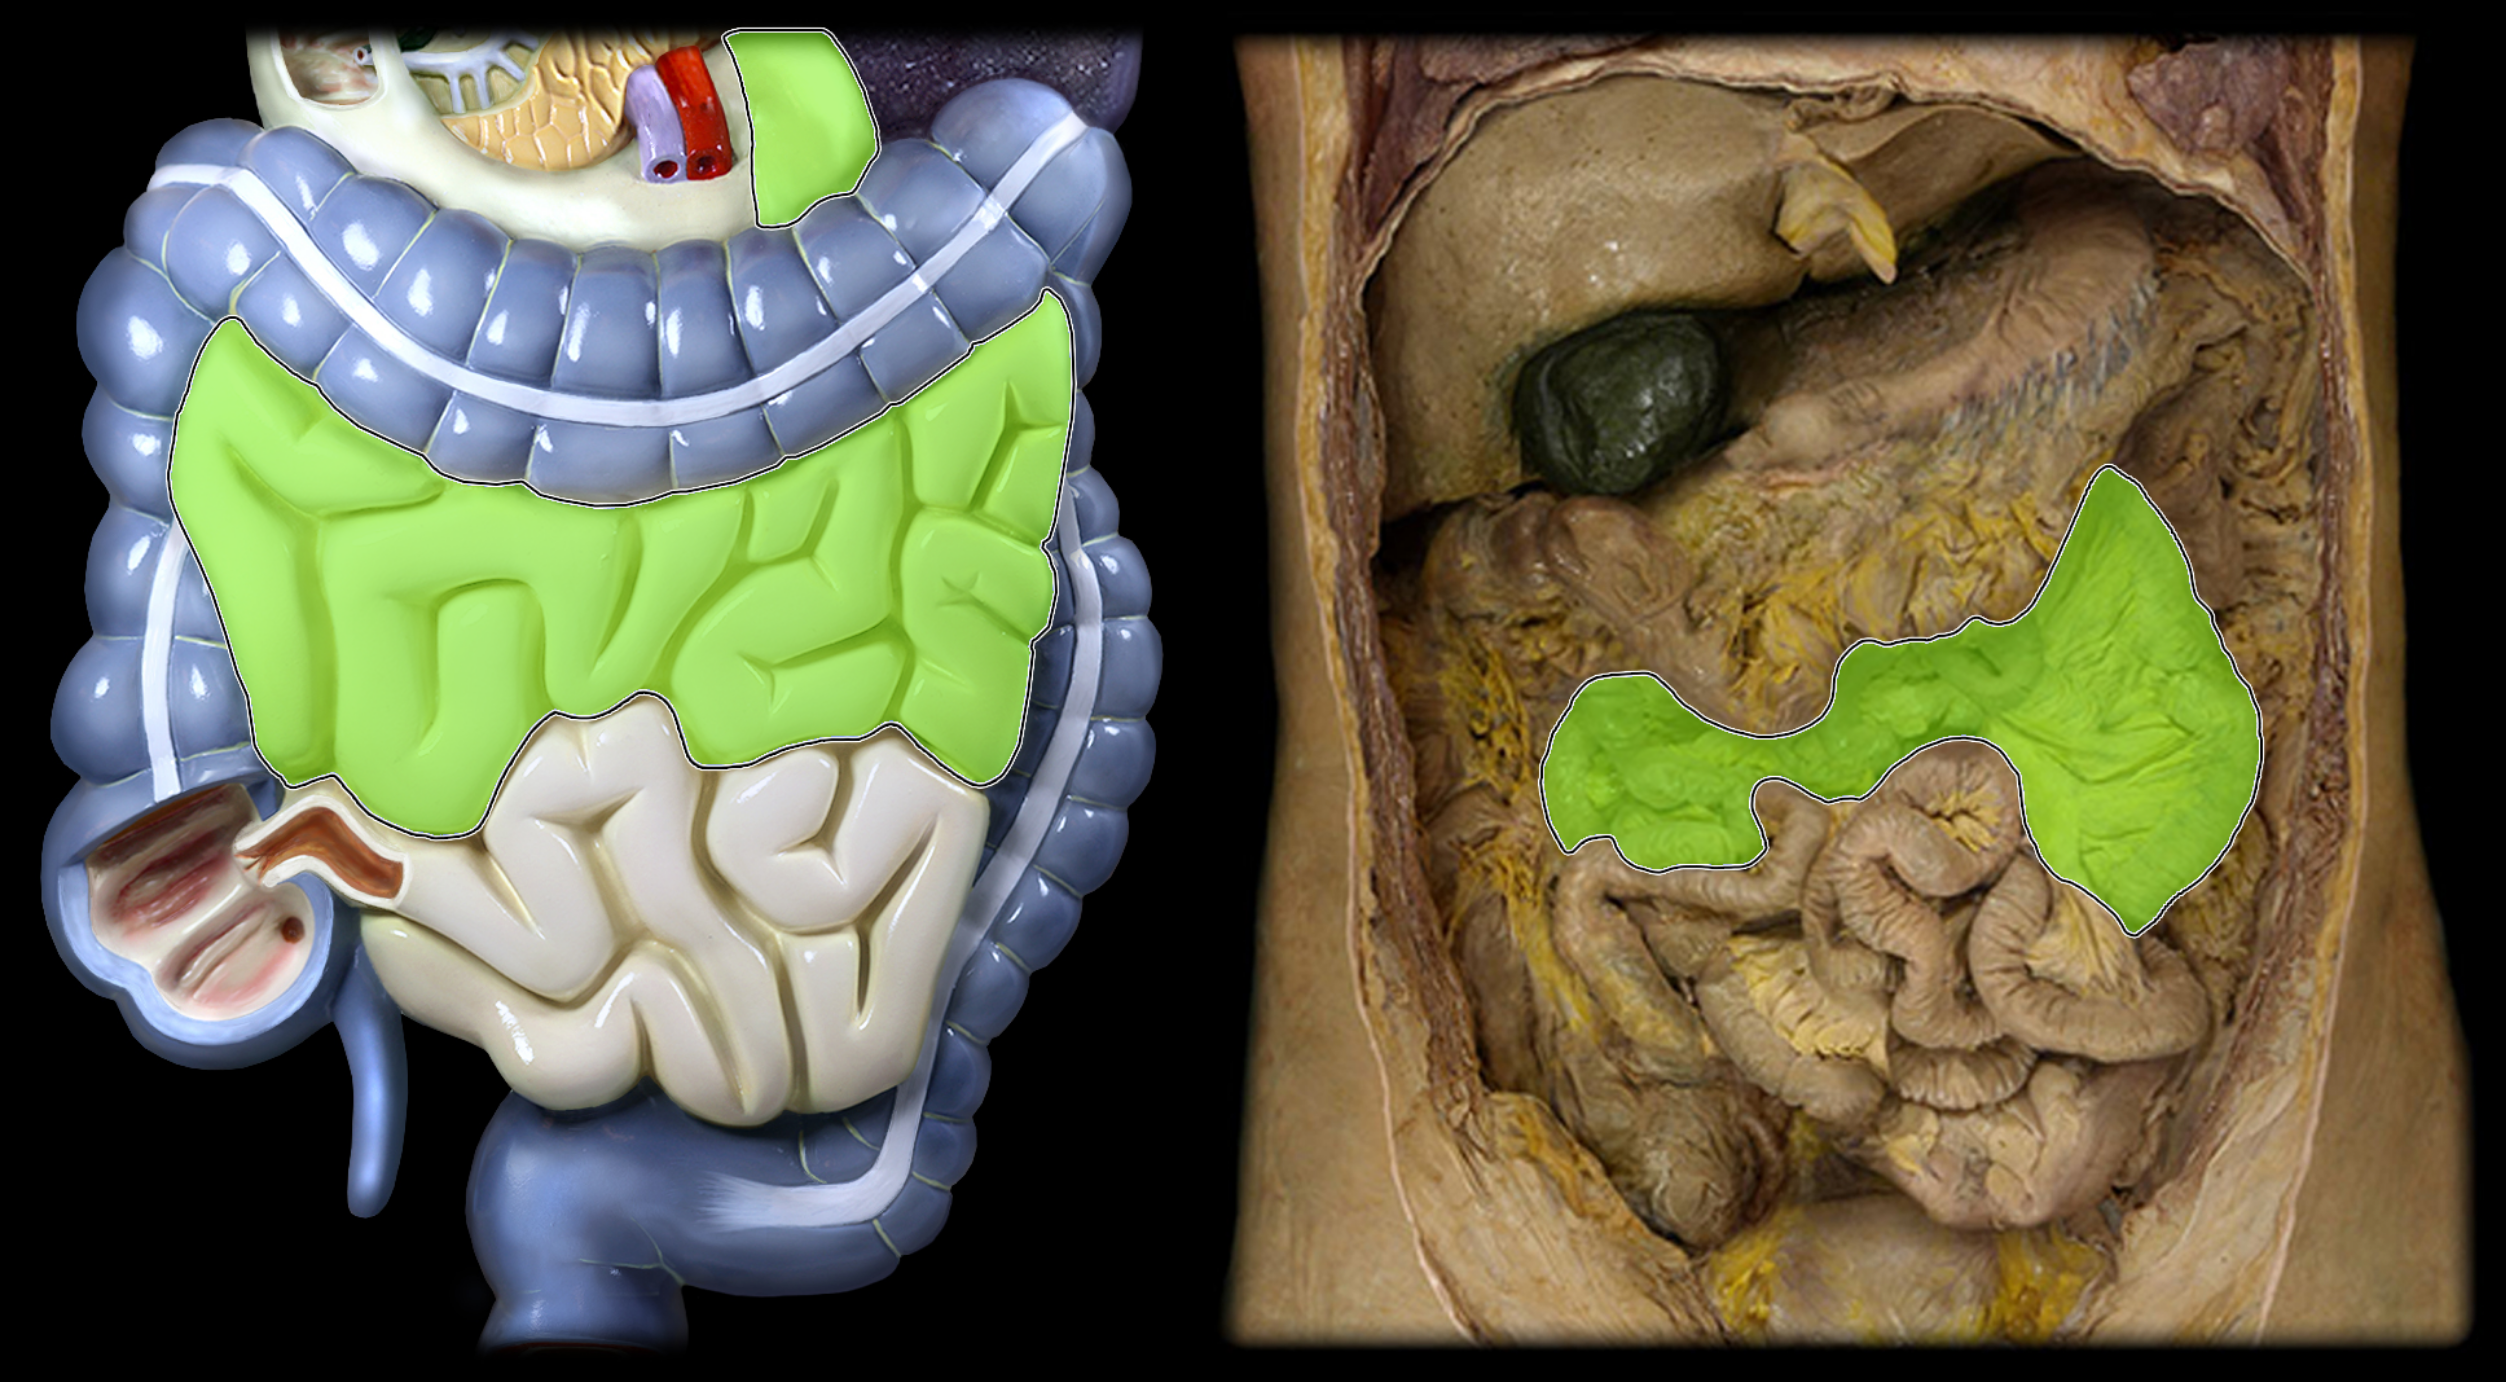

Jejunum

Ileum